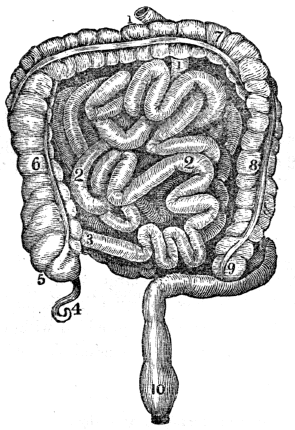

| 13. | Anatomy of the Digestive Organs, | 113 |

| 14. | Physiology of the Digestive Organs, | 124 |

| 15. | Hygiene of the Digestive Organs, | 129 |

| 16. | Hygiene of the Digestive Organs, continued, | 142 |